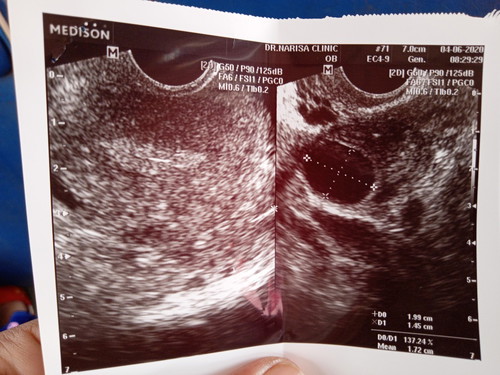

ตรวจครรภ์เจอขีดจางๆ แต่ไปตรวจกับหมอมา กับว่า ไข่ยังไม่ตก รอบเดือนเลื่อน1เดือน10วัน ไม่ท้อง ไข่ตกช้า หมอบอกเชื่อที่ตรวจไข่หรือเทสไม่ได้จริง